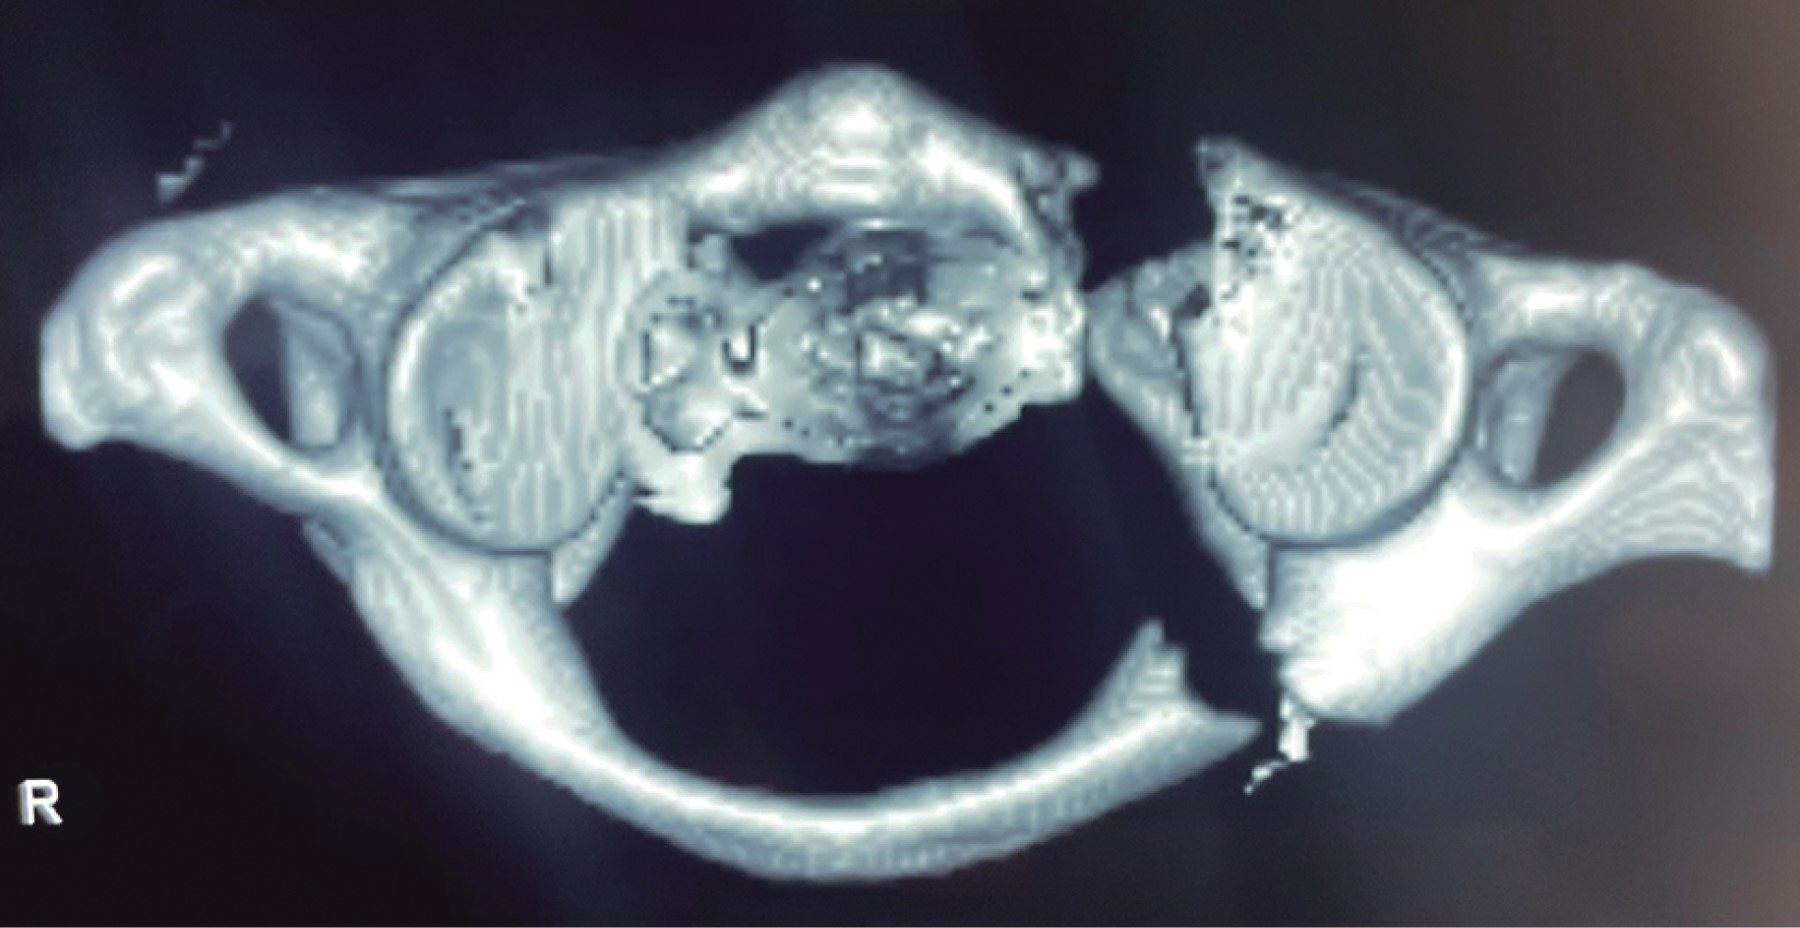

Se presenta el caso de un paciente masculino de 33 años de edad, sin comorbilidades, que acude al servicio de urgencias por presentar cervicalgia de dos semanas de evolución posterior a un accidente en motocicleta. Las radiografías iniciales tomadas en el hospital de primera atención no fueron valorables para diagnóstico; se toman radiografías y tomografía axial computarizada (TAC) de columna cervical (Figuras 1, 2 y 3), diagnosticando fractura de C1 y C7 donde se observa fractura por compresión de C7 AO B2 y C1 con fractura de arco anterior y posterior izquierdo con desplazamiento coronal > 7 mm de la masa lateral izquierda. En la resonancia magnética T2 axial, se observa lesión del ligamento transverso. En resonancia magnética simple se observa fractura de cuerpo vertebral de C7, con compromiso de conducto raquídeo